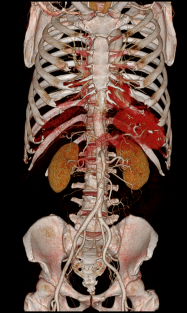

Chẩn đoán hình ảnh mô mềm tiên tiến cho vùng bụng.

Tăng cường độ tương phản I-ốt.

Hỗ trợ đánh giá an toàn cho bệnh nhân.

Đảm bảo hình ảnh chất lượng cao.